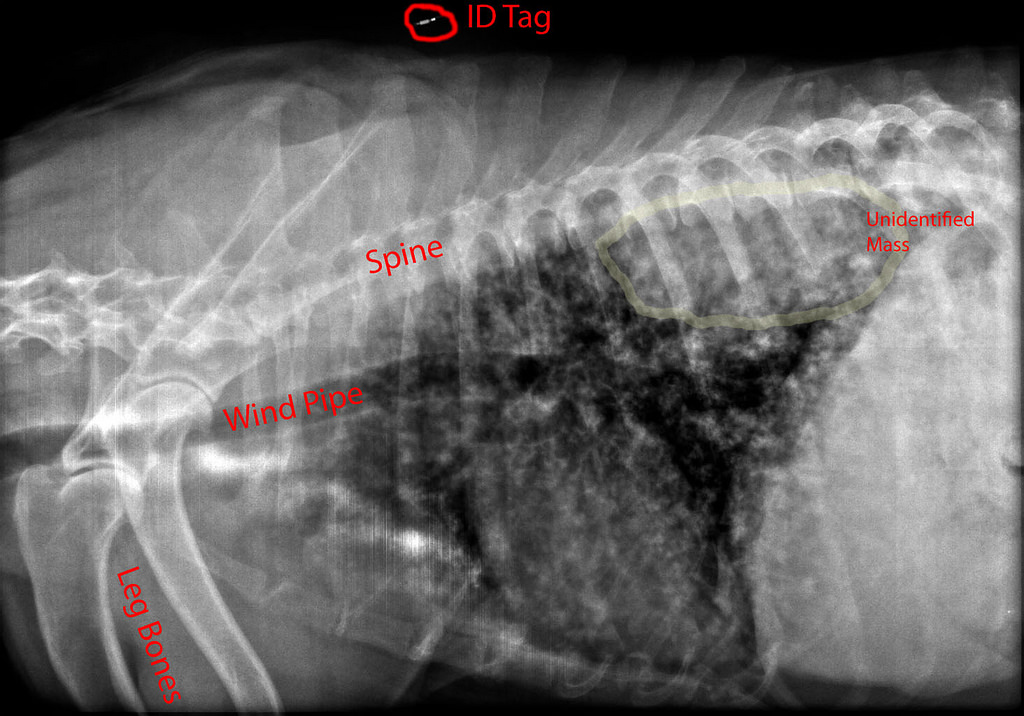

• X Ray Lung Cancer Dogside View Stock Photo Edit Now 1285308907

• The Benefit Of Three View And Left Lateral Thoracic And Abdominal Radiographs Tips For Taking Radiographs In Your Veterinary Practice 2 Important Tips For Taking X Rays In Your Veterinary Practice Tips For Taking X Rays

The Benefit Of Three View And Left Lateral Thoracic And Abdominal Radiographs Tips For Taking Radiographs In Your Veterinary Practice 2 Important Tips For Taking X Rays In Your Veterinary Practice Tips For Taking X Rays Jumbo Coloring Books For Adults